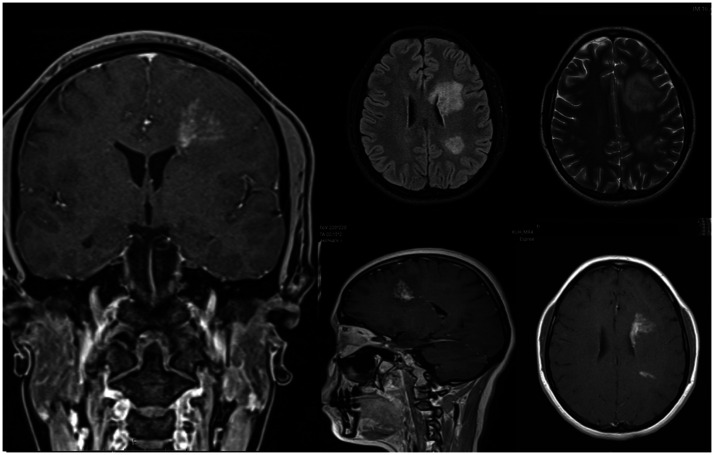

Case: We present a unique case of SLIPPERS observed in a 26-year-old woman with no notable medical or familial background. Laboratory findings ruled out certain diseases from the list of differentials and cranial MRI showed T2 hyperintense areas with linear-patchy enhancements, a pattern consistent with SLIPPERS syndrome. Consequently, patient was diagnosed with SLIPPERS syndrome and received methylprednisolone therapy.